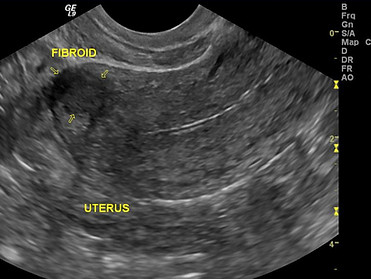

Pelvic-GYN Ultrasound

Pelvic Transabdominal (TA) and Pelvic Transvaginal (TV) Ultrasounds are both performed in our office. A Pelvic Complete does include both TA and TV but some physicians will order just one method.